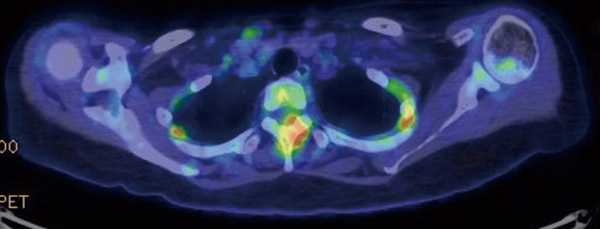

がんは進行すると全身のさまざまな臓器に転移しますが、骨は転移しやすい臓器の一つです。骨転移は主に肺がん、乳がん、前立腺がんでみられますが、疼痛、病的骨折、脊髄圧迫による神経障害、高カルシウム血症などさまざまな合併症を起こします。その結果、がん治療が続けられず治療成績を悪化させたり、本人の生活の質(QOL)を低下させうる、注意すべき病態です。

骨転移を抑制するためには、もとのがんの治療とあわせて、支持療法として骨修飾薬の適切な使用が重要です。ビスフォスフォネート薬であるゾレドロン酸(ゾメタ®)および抗RANKLモノクローナル抗体製剤であるデノスマブ(ランマーク®)が使用されます。日本ではいずれも悪性腫瘍の骨転移または多発性骨髄腫の骨病変に保険承認となっていますが、多発性骨髄腫では抗腫瘍効果(がんの抑制効果)も示されており、より積極的に導入されます。